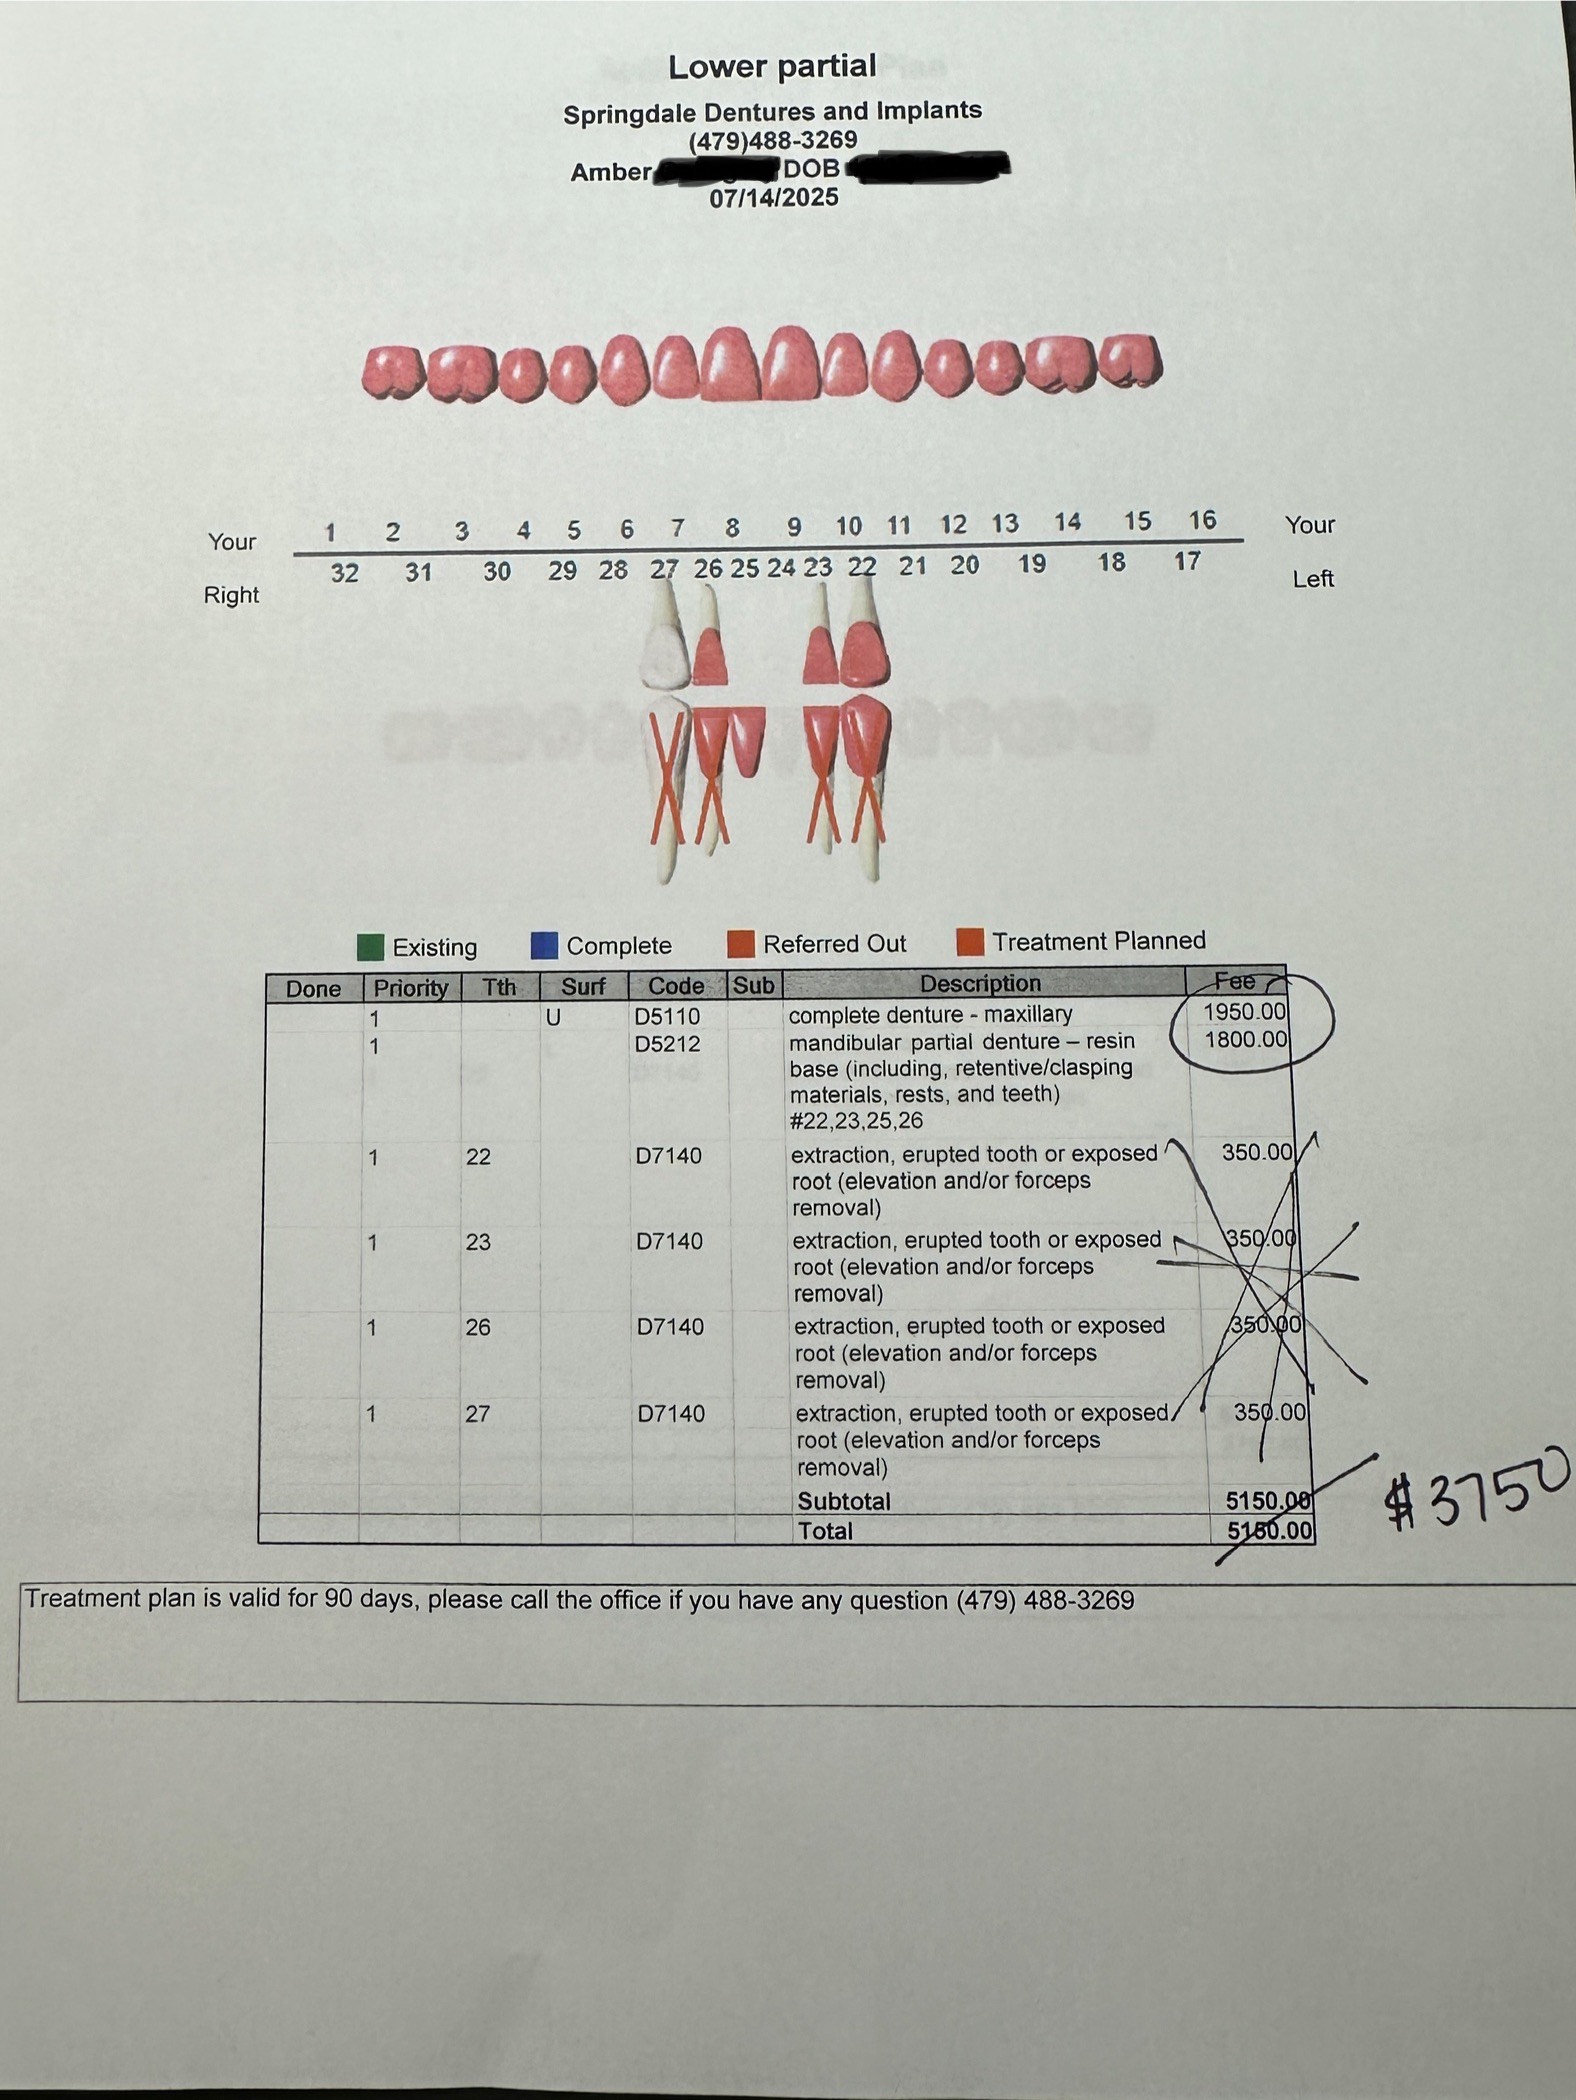

Hello. My name is Cynthia and I am making this GoFundMe for my wife, Amber. She is in desperate need of some dentures. She has been struggling with several dental issues for years. She has degenerative gum disease, and this has caused her to have all but four of her teeth removed. She is unable to eat meals and constantly chokes because she cannot break down her foods. It also affects her mental health in a negative way. We found a dentist that will make these for her, but since we live on a limited income, we cannot afford to get them. I have attached a copy of the quote from the dentist. Please help us get Amber's smile back!